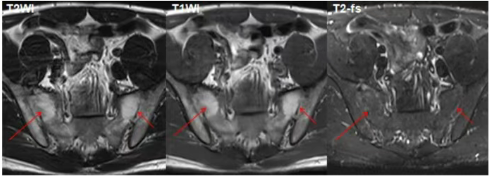

MR:可显示软骨下骨、韧带、滑膜和关节囊的软骨和急性炎症活动的初期变化,从而进行早期诊断。研究表明,MR在检测早期结构变化方面具有与CT类似的敏感性,并且对于评估脂肪沉积具有更好的灵敏度。MRI显示的骨髓水肿可为强直性脊柱炎的诊断及病情评估提供重要信息,且MRI现在正逐渐用于评估抗炎药物的疗效。

活动性炎症病变(早期改变)包括骨髓水肿,滑膜炎,关节囊炎,附着点炎。

结构性破坏(慢性改变)包括软骨下骨硬化,骨质侵蚀,关节周围脂肪沉积,骨桥、关节强直。